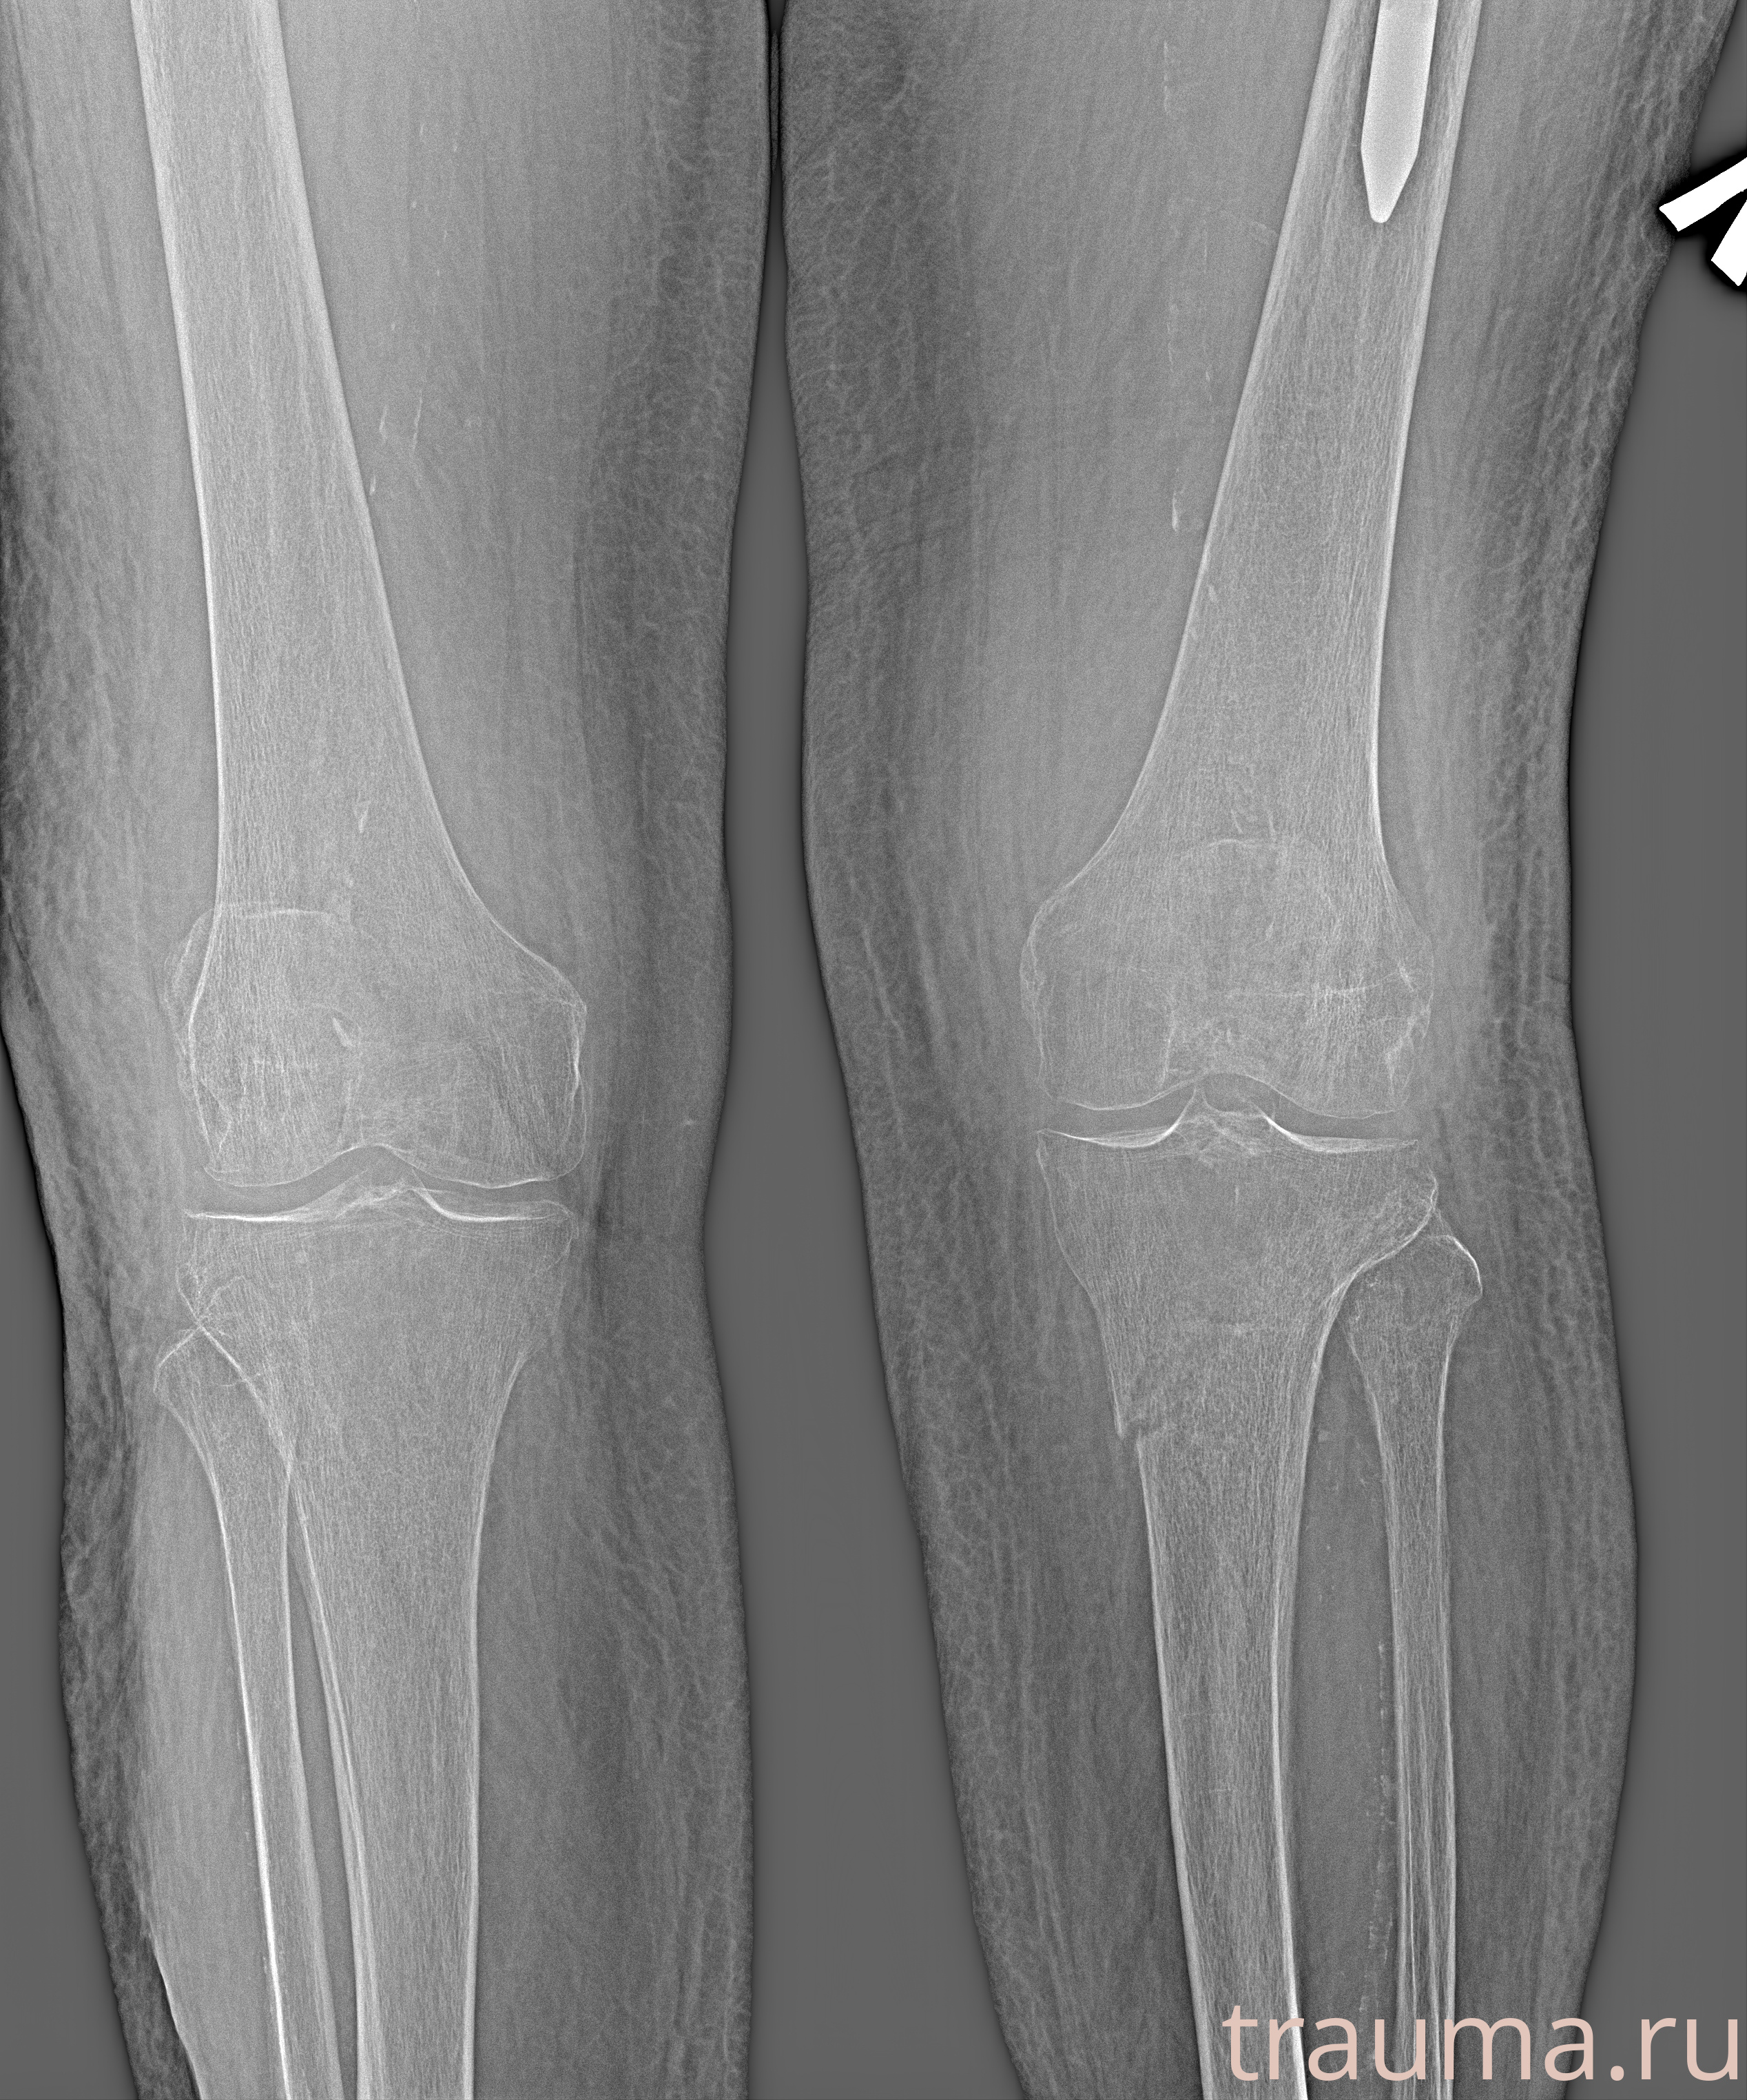

Рентген на дому: по вашему адресу приезжает врач-рентгенолог, травматолог-ортопед с мобильным рентгеновским аппаратом, проводит диагностику травмы или заболевания, делает необходимые рентгенограммы, дает рекомендации по дальнейшему лечению. Получить качественные снимки в домашних условиях возможно благодаря уникальной методике, разработанной МосРентген Центром для института  Склифосовского